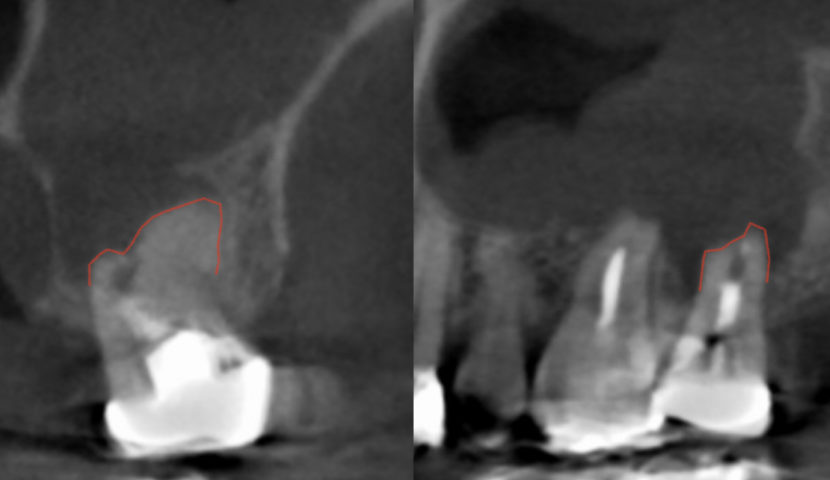

インプラント治療は、近年長期安定性が見込める治療になってきました。10年予後が下あごで99%、上あごで96%とも言われております。当院では、過去に歯を失ってしまって後悔されている方に対しても、お一人お一人にとってのベストな歯科治療をご提供できるようにしております。